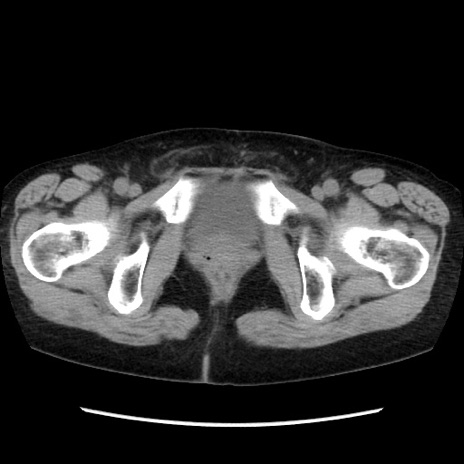

冠状断像

【症例】40歳代 女性

【主訴】上腹部痛、嘔気・嘔吐

【現病歴】約9時間前頃から急に上腹部痛、嘔気、嘔吐が出現。改善しないため救急要請。

【既往歴】子宮頚癌(広汎子宮全摘術、放射線療法)、腸閉塞

【身体所見】腹部:平坦、軟、腸雑音亢進、上腹部を中心に腹部全体に圧痛あり。

【データ】WBC 8400、CRP 0.03